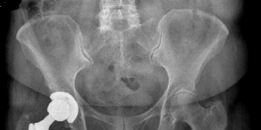

- This final image likely represents a post-operative radiograph of a successfully implanted uncemented acetabular component, demonstrating good position and fixation.

Clinical & Radiographic Imaging